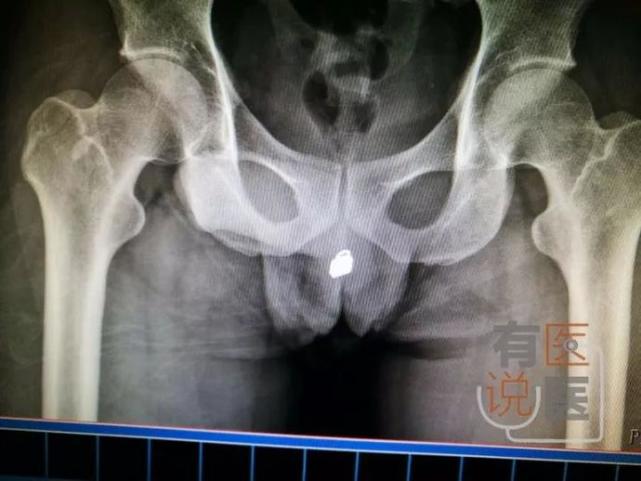

男子将锁通过尿道塞进膀胱紧急就医, 网友惊叹: 他怎么做到的

男子把锁头从尿道塞进膀胱 锁加上锁柄长达2厘米_大渝网_腾讯网